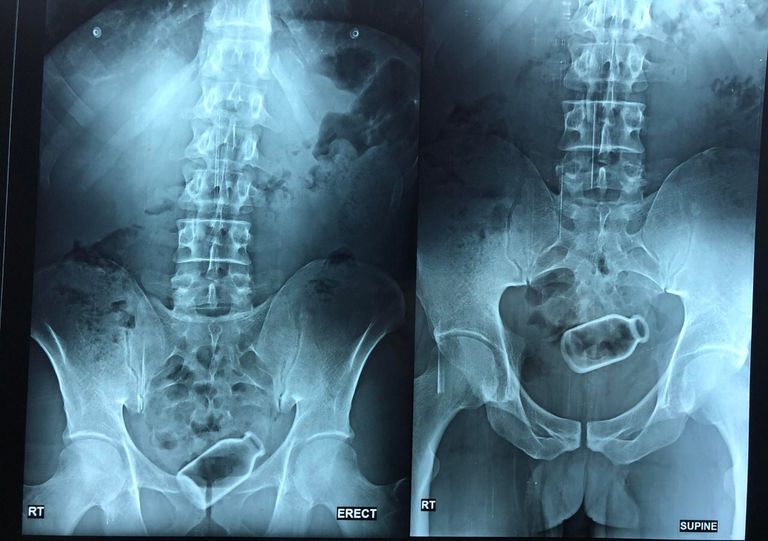

تمكن فريق طبّي مصري، الجمعة، من استخراج زجاجة من قولون مريض، دخلت بسيناريو خيالي، واستقرت داخله لمدة أسبوعين.

وعن تفاصيل الجراحة، أكدت أن الزجاجة كانت مستقرة ولم تثقب في القولون، وكانت على بعد 20 سم من فتحة الشرج، وهذه مسافة بعيدة نسبيا، ومن الطبيعي عند وجود جسم غريب في القولون يكون قريبا من فتحة الشرج، وعادة يتم استخراجه عن طريق الجراحة أو اليد.

وأوضحت أنّه عن طريق الآلات والأجهزة الطبية، ودون جراحة، تمكنا من استخراج الزجاجة من قولون المريض في عملية استغرقت حوالي ساعة.